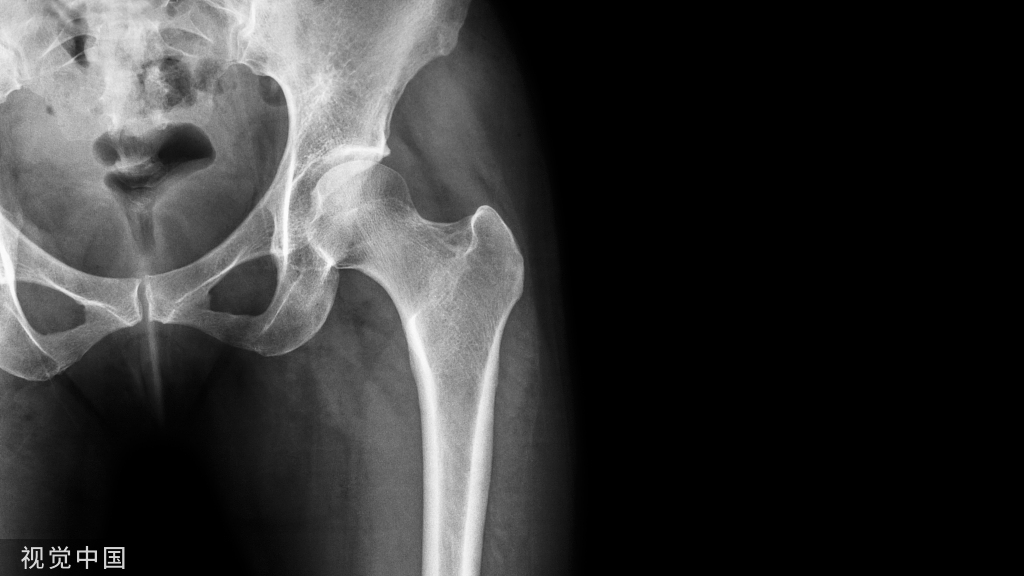

经髂腹股沟入路髋臼骨折手术注意事项之一二!

髂腹股沟入路,顺行后柱螺钉是固定后柱的最佳方式,它可经塑形好的钢板置入,也可于钢板外置入。

Via Ilioinguinal approach, antegrade posterior column screws are the optimal implants to stabilize the posterior column, which can be placed either through the contoured plate  or not.